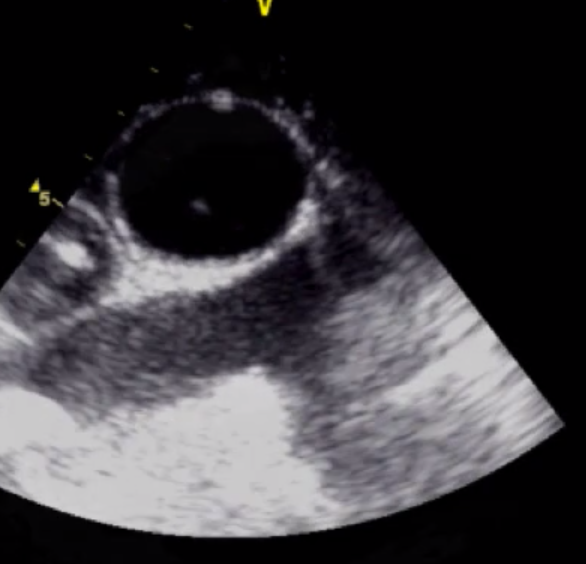

Label the Long axis of the Epiaortic Exam

Aorta on top

Left = Proximal

Right = Distal

RPA (Bottom screen)